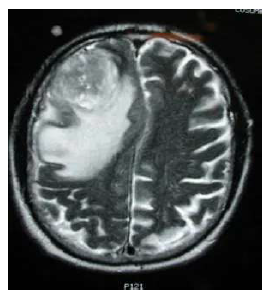

Glioblastoma Multiforme

Grade 4 Astrocytoma

• Most aggressive tumor form (grows in 1-2 months)

• Average survival rate from diagnosis approx. 2 years

• Higher Incidence in white individuals